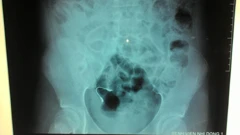

Ngủ dậy, phát hiện niềng răng lọt vào bụng